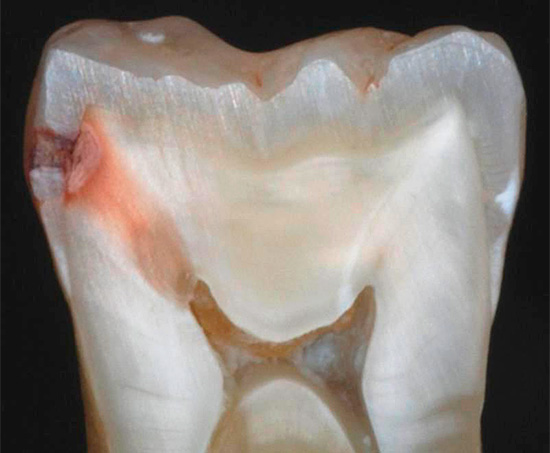

Nella foto sotto - la carie interna sui tessuti sotto lo smalto distrutto. Questo è un tipo tipico di malattia che si sviluppa all'interno del dente. Le aree scure della dentina interessata sono chiaramente visibili:

È il cambiamento di colore dei tessuti danneggiati dalla carie che è il principale segno diagnostico della malattia. Nella stragrande maggioranza dei casi, è proprio sui punti neri sullo smalto o sulle fessure che il medico fa in modo inequivocabile la diagnosi di carie.